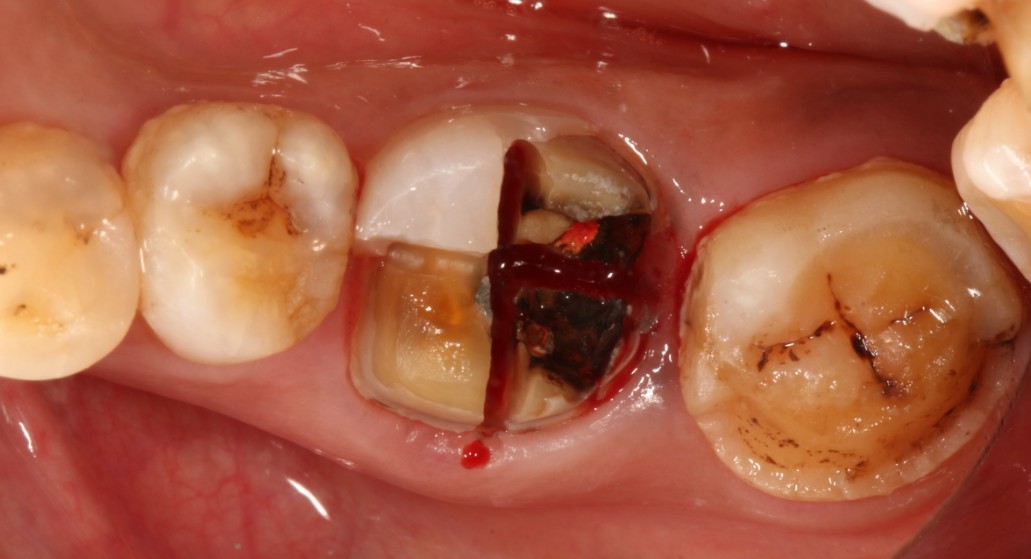

患者右下后牙根管治疗十年后咬合不适,x片显示近中根尖阴影较大,根折,患牙不能保留,患者非常焦虑拔牙,更怕种植牙,要求拔牙后即刻种植,通过CBCT检查,确定剩余骨量足够多,可以即拔即种植;患者知情同意下,完成即拔即种,四个月后CEREC数字化扫描,当天完成了牙冠修复,同时邻牙也完成嵌体修复!有图有真相。